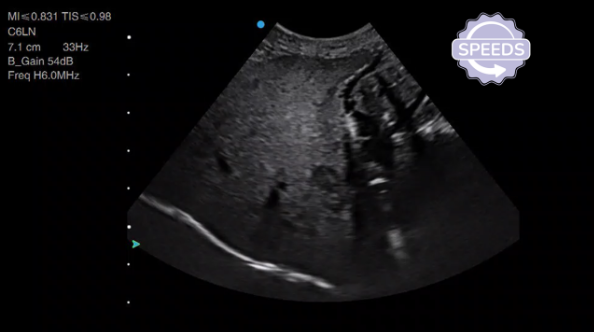

Hypoechoic lesion in the caudal liver.

When You Find a Focal Lesion: Run a Mini-SPEEDS.

Once you've found a focal or multifocal area that's different, it's really important to describe that lesion in detail. You do this by repeating SPEEDS on the lesion itself:

S - Size: Measure height, width, and depth. You really need three measurements (two planes) to understand how big this lesion is. This measurement is key—if you don't pursue further treatment immediately, monitoring the lesion for size change is a potential next step, but you need that baseline measurement documented.

S - Shape: Scan through the lesion in two planes. Is it round? Irregular? Elongated?

P - Position: Which side of the liver? Which lobe? Associated with the gallbladder or other structures?

E - Echogenicity and Echotexture: In the example from our video, the lesion is quite hypoechoic compared to the rest of the liver, but it's quite homogeneous within itself.

E - Edge: Is it poorly defined or well-defined? Does it have a regular edge or irregular border?

D - Dynamics: This is really key. Think about blood flow in the lesion. Put power Doppler on to assess whether there are any blood vessels. In our example, you can see one vessel entering the lesion.

S - Sampling: Is this something you could safely sample? Are there big blood vessels in the way? Other organs you'd have to go through? Is the distance reasonable for a needle to extend to?

All of these observations should be noted in your report.